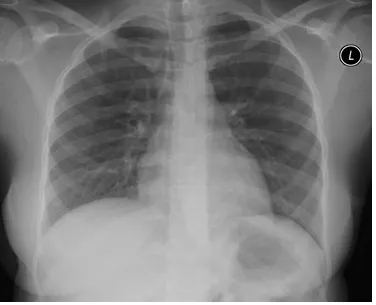

39세 여성이 5개월 동안 지속되는 마른 기침으로 내원했다. 기침 증상은 특히 저녁 식사 후와 잠자리에 들기 전에 더욱 심해진다. 환자는 비흡연자이며, 코와 부비동 검사를 포함한 신체진찰에서 특이 소견은 발견되지 않았다. 환자의 가슴 X선 사진이다. 다음 중 가장 적절한 검사는?

• 신체진찰, CXR 상 특이 소견이 없고, 흡연력이나 ACEi 등 기침을 유발할 만한 약물 복용력도 없다.